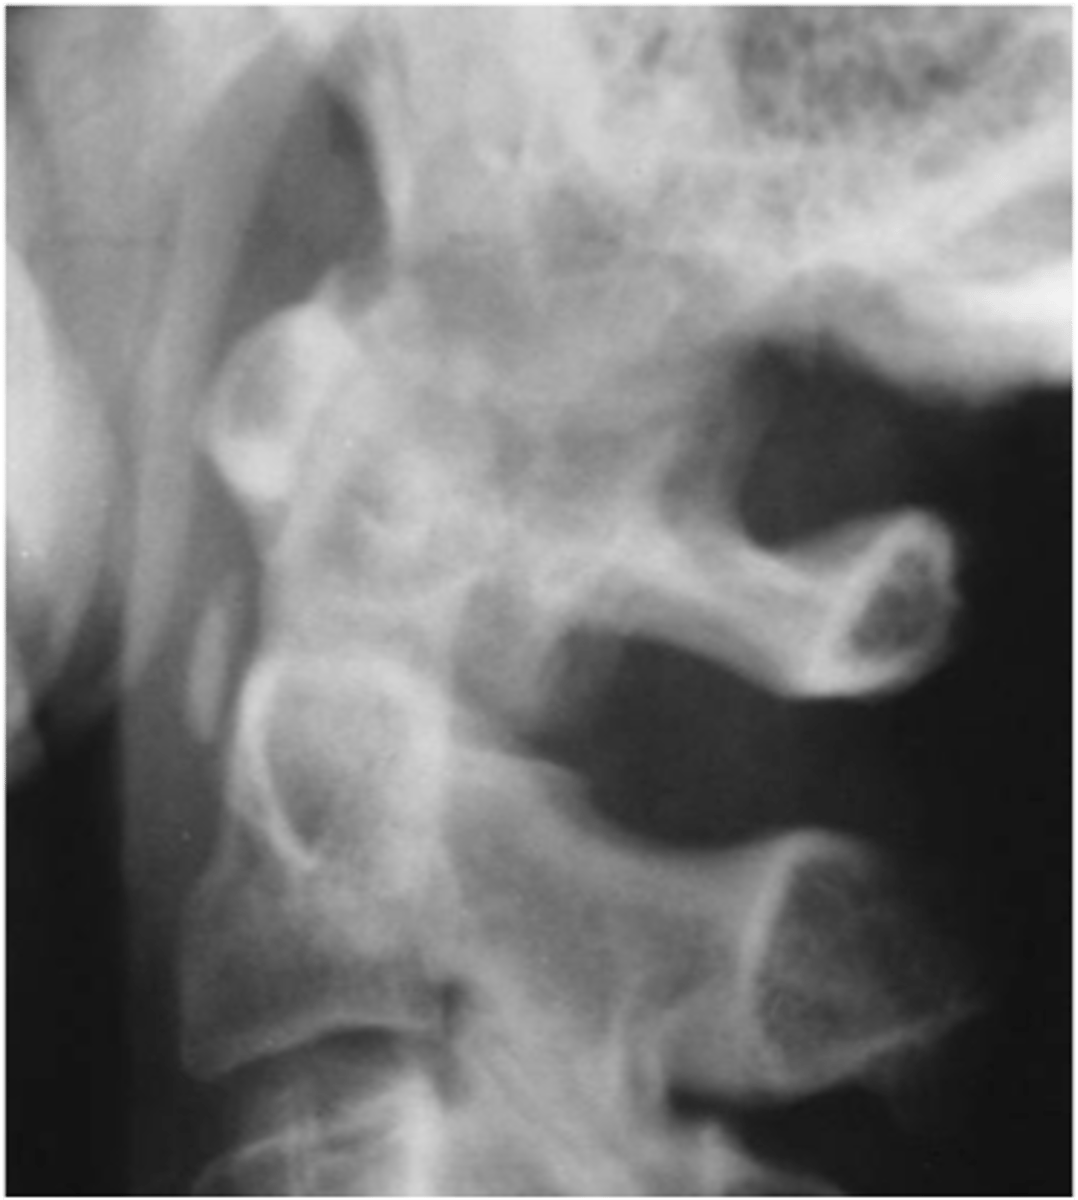

- Dense soft tissue tophi (swelling)

- Bone erosions

- Overhanging margin sign

- Secondary degeneration

- 1st MTP MC joint

State the radiographic findings of gout